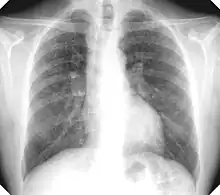

La silicosis simple es la forma clínica más frecuente con mucho. Muestra opacidades redondas (las más frecuentes) y/o irregulares en radiografía simple póstero-anterior de tórax (Rx). No suele producir alteraciones funcionales con significación clínica ni disminuye la esperanza de vida, siempre que no evolucione a complicada.

El diagnóstico se basa en una historia laboral significativa y hallazgos típicos en Rx. La OIT (Organización Internacional del Trabajo) ha elaborado una normativa con el fin de clasificar, describir y codificar las alteraciones radiográficas, atribuibles a neumoconiosis y facilitar su comparabilidad en estudios epidemiológicos, sin pretensiones o connotaciones legales, aunque también se usa en la clínica; la edición del año 2000 se basa en la comparación de la Rx del paciente con placas modelo que aporta la organización.[8]

Las pequeñas opacidades redondas se clasifican según su diámetro como p (las más pequeñas), q (las que exceden 1.5 mm) y r (las que exceden 3 mm y no pasan de 10 mm) y las irregulares como s, t, u en función de su anchura (equivalente al diámetro en las redondas). La cantidad o profusión se categoriza de 0 a 3.

Se establece una notación combinada en función de la profusión con 12 categorías desde 0/- (pulmón completamente limpio) 3/+ (la máxima profusión imaginable); por ejemplo 1/2 q/t. La primera cifra y la primera letra serían las más probables.

La OIT clasifica las masas de FMP) según su diámetro mayor como A (exceden 10 mm), B (aisladamente o sumadas exceden 5 cm) y C (exceden un área equivalente a la de lóbulo superior derecho.

En caso de dudas diagnósticas se puede recurrir a la Tomografía Computada de Alta Resolución (TACAR) que se ha mostrado más sensible y específica para el diagnóstico.[9] Somete al paciente a mucha más radiación que la Rx y no debe usarse como prueba diagnóstica de primer nivel sino para aclarar dudas. La TACAR permite comprobar cómo las masas de FMP se originan frecuentemente en región subpleural de zonas apicales posteriores desplazándose progresivamente de la pleura —signo del desprendimiento—.[3]